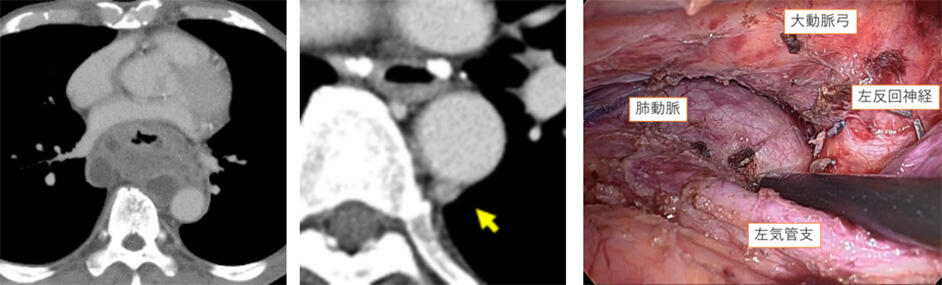

食道は体の中心よりも左にあり、接する大動脈はより左にあります。そういった奥深い所にべっとりと固着する癌をいつも通り右側から手術するのはとても大変で難しいものです。我々は腹臥位鏡視下/ロボット手術の低侵襲性は固定概念を乗り越えることができます。左側から手術を開始すると、癌がべっとりと大動脈に接しているところは一番手前にあります。つまり一番切除が難しい場所が手前にあるので、難易度が著しく緩和できるのです。また大動脈弓下の左反回神経(声を司る神経)の基部は右側からは深く手術操作を入れることは怖い場所でなかなかできませんが、左では手前にあるので、癌が入り込んでいてもしっかり切除することができます。さらに大動脈左側のリンパ節転移は右からは見えないので、切除不能とされていましたが、左では容易に切除できます。

次に右側に回って続きの食道癌切除をおこなって手術を完遂します。外科医は清潔ガウンのまま移動するだけなので、タイムロスはありません。術後経過も通常手術と変わりはありません。TLR-MIEは根治切除のための有用なオプションです。

大動脈に固着する癌・大動脈左側のリンパ節転移・大動脈弓の下縁は全て取除できる。